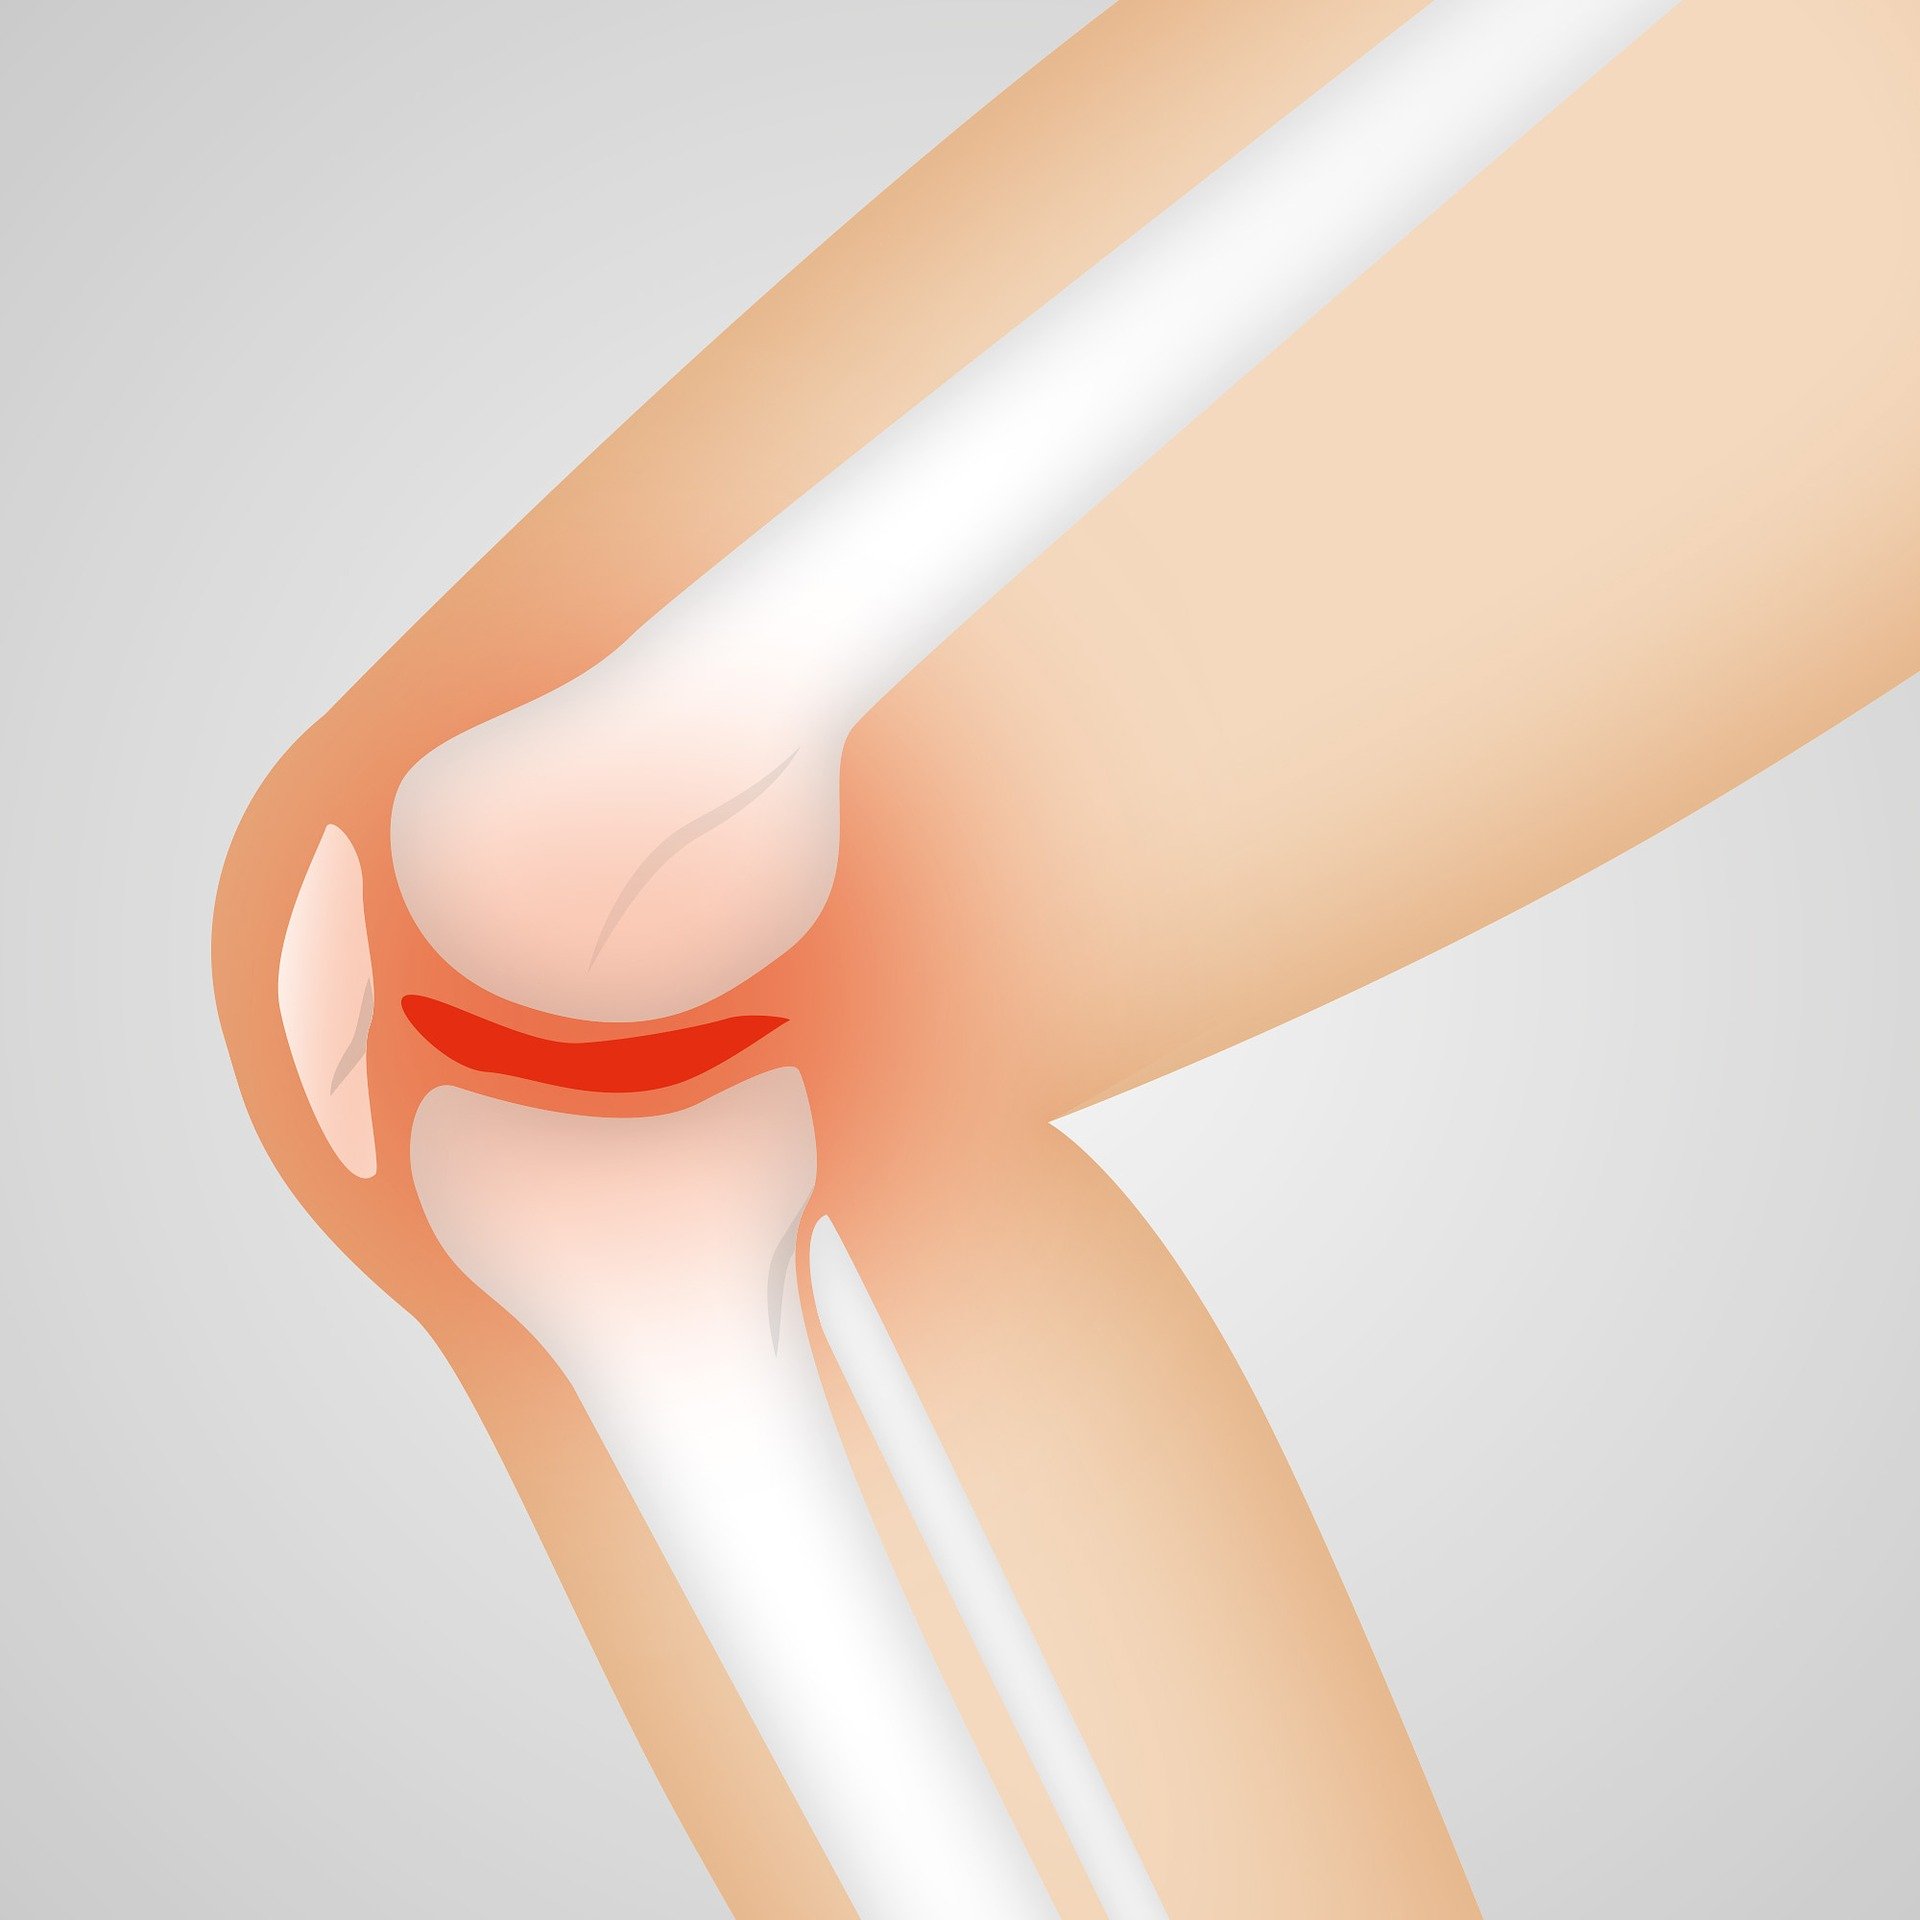

연골이란 무엇인가?

연골은 인체 내부의 연결 조직 중 가장 튼튼한 조직 중 하나입니다. 강력한 저항성, 뛰어난 내구성 등 다양한 기능을 함께 하며 우리 몸이 움직일 때 중요한 역할을 합니다. 뼈를 매끄럽게 움직이기 위해 필요한 쿠션처럼 기능하기 때문에 우리 몸에 있어서 매우 중요한 역할을 합니다. 이처럼 연골은 제한된 양의 영양소를 유지하면서 수백 번의 반복적인 부하를 견뎌 내야 할 수 있도록 설계되어 있습니다.

연골은 우리 몸에서 쿠션 역할을 하므로, 강력한 충격을 흡수하고, 뼈의 접촉 부분에 더 많은 마찰을 방지하고, 원활한 움직임을 유지합니다. 연골의 재생 및 관절염 예방을 돕기 위해 저분자 콜라겐 펩타이드 외의 다른 영양소도 사용됩니다.